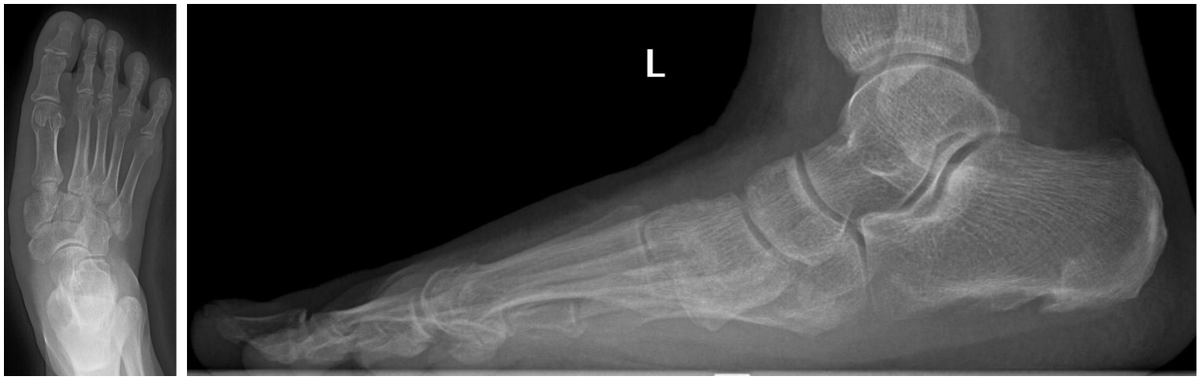

Перед специалистами травматолого-ортопедического отделения №6 Новосибирского НИИТО им. Я.Л. Цивьяна Минздрава России стояла задача коррекции сложной посттравматической деформации. Исходная травма привела к стойкому смещению костных фрагментов, что выражалось в грубой деформации стопы, болевом синдроме и нарушении её опорной функции.

До операции